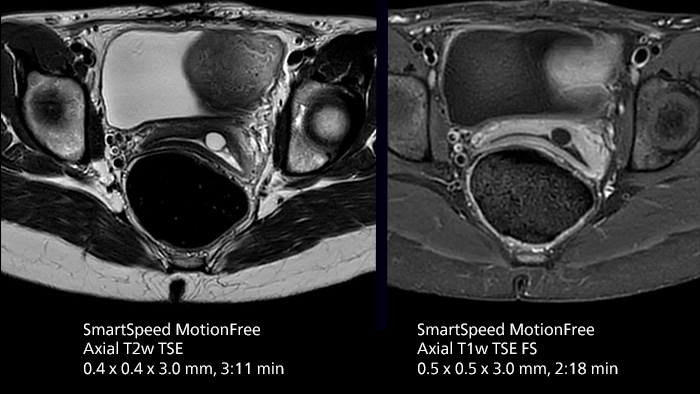

After using Philips SENSE, Mermaid Beach had adopted Compressed SENSE that offers a k-space sampling approach to speed scans while preserving details. “And now SmartSpeed enables denoising the sparse under-sampling in a new way that has allowed us to increase acceleration and bring image quality to a whole new level,” notes Kennedy, “It’s truly revolutionized our MRI work space, especially for difficult patients.”

Philips SmartSpeed has multiple approaches to denoising. Raw k-space data, coil sensitivity and coarse background information are all used and reconstructed with artificial intelligence (AI) to provide true resolution in shorter scan times1 with more sequences. Kennedy states, “I noticed that since the introduction of SmartSpeed, our day is a lot less stressed. When complicated exams need extra time, we just get on with them. And if we need to do something new or extra, we have the time for it and our workflow is still a lot more efficient.”

In addition to workflow benefits, Kennedy highlights the improvement in their diagnostic confidence. “The quality of output is so much higher than what we believed was possible, and it is very consistent across multiple patients. SmartSpeed made it feasible for us to include extra sequences in our exams and still maintain routine scanning times. This allows us to make a surprising number of diagnoses that we couldn’t have appreciated before with our previous protocol. We’ve gotten an extremely positive response from our referrers.”